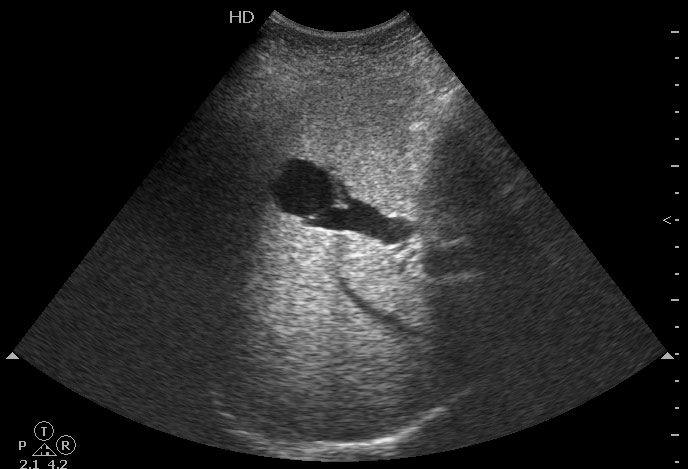

УЗИ: портосистемный внутрипеченочный шунт

Больная с с желтухой, направлена на УЗИ для уточнения ее причины. Никих операций до обращения в стационар не было.